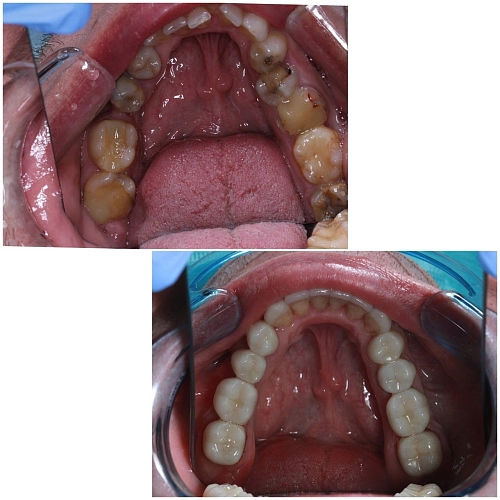

Клинический случай:

У пациента значительная потеря зубов, что привело к изменению прикуса и функциональным нарушениям.

2. Ортодонтическая коррекция: В данном случае коллегиально было принято решение о необходимости ортодонтического вмешательства для достижения правильного смыкания и восстановления функций.

3. Установка имплантов: На этапе ортодонтического лечения были установлены импланты в области отсутствующих зубов, что позволило создать опору для дальнейшего протезирования.

4. Тотальное протезирование: После завершения ортодонтического этапа и интеграции имплантов было проведено тотальное протезирование с поднятием высоты прикуса. Это позволило восстановить функциональные и эстетические параметры.

Данный клинический случай подчеркивает важность комплексного подхода к лечению пациентов с нарушениями прикуса и функциональными проблемами. Ортодонтическое вмешательство в сочетании с имплантацией и протезированием может существенно улучшить качество жизни пациента.